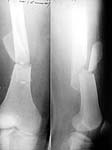

Just have a look at the attached X-rays. The patient had ipsilateral tibial fracture also which was also nailed and locked. The pre operative X.ray was taken in Jan 2001 and the other two x rays were taken in July 2001. These fractures were close nailed.